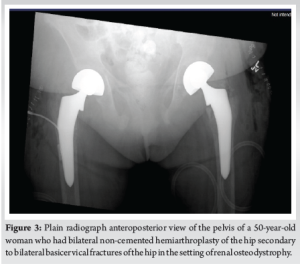

28 days after admission and initial presentation, the patient consented to bilateral non-cemented hemiarthroplasties performed through the direct anterior approach with the patient supine. The surgeon felt that less patient movement in this approach (as compared to the lateral decubitus position) would make the surgery more efficient due to decreased blood loss and a lack of available blood products. On the right, a size 7 collared stem minus head with a 51 bipolar component was used. On the left, a size 7 collated stem plus 0 head with a 52 bipolar component was used. Both implants were Medacta. Bilateral release of hip contractures with capsulotomies with removal of multiple bone fragments was performed. Femoral head bone biopsies were also taken. The tensor fascia latae was closed with a #1 Vicryl followed by 0 Vicryl staples. A Prevena vacuum dressing was applied with excellent suction. There were no complications during the procedure as the patient was successfully extubated and transferred to the recovery room. On post-operative day 7, the patient was able to bear weight after sitting at the edge of the bed. The patient reported 8/10 right knee pain but could not give a numerical value for back pain. The patient agreed to participate in physical therapy upon discharge. Post-operative AP X-rays of the pelvis can be seen in (Fig. 3).

During her first post-operative clinic visit, the patient was alert and oriented, ambulating with a front-wheeled walker under supervision. On physical examination, the surgical wounds were clean and dry without signs of infection. She reported reduced pain in the hips and improved mobility compared to her pre-operative status. No dislocations or implant-related complications were noted on follow-up radiographs. The patient expressed satisfaction with the outcome and was referred for outpatient physical therapy to continue rehabilitation. Laboratory studies at follow-up showed stable Hb levels and improved renal parameters with dialysis. The patient’s last known follow-up was approximately 6 months post-operative. The patient resided in a nursing home, demonstrated improved mobility, and maintained stable prostheses with no reported complications.